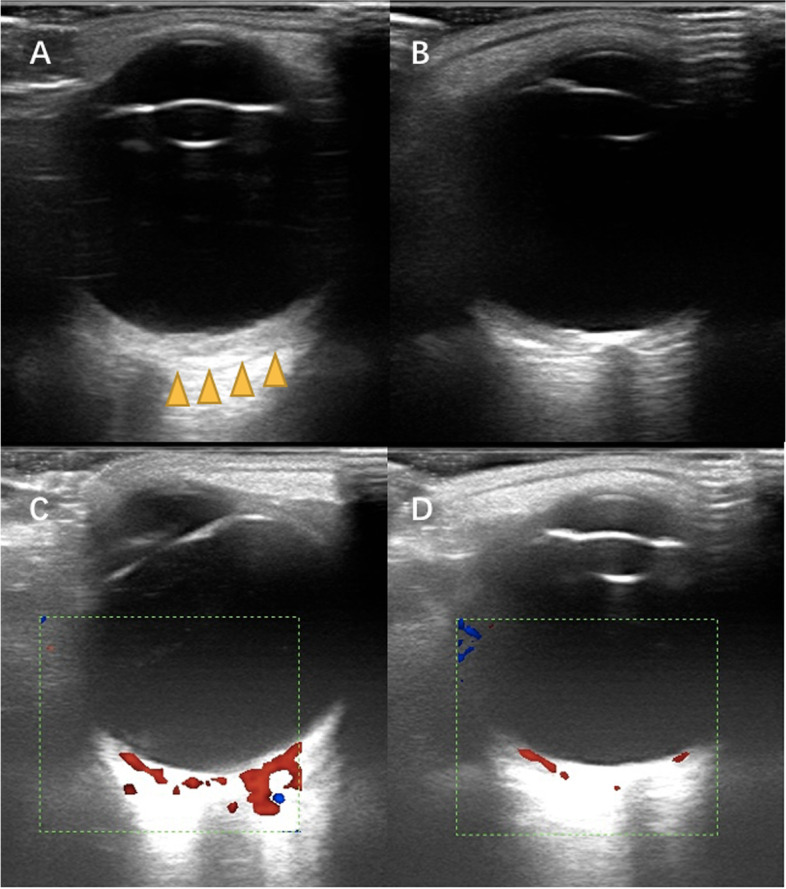

Conjunctival/episcleral haemangioma (Fig. 2C) occurred in 30 eyes of 25 patients. Twenty patients had unilateral conjunctival/episcleral haemangioma and ipsilateral glaucoma. Five patients had bilateral conjunctival/episcleral haemangioma. Of these five patients, one was diagnosed with bilateral glaucoma and bilateral PWS; two had bilateral PWS, but unilateral glaucoma; and two patients had unilateral PWS and glaucoma, but bilateral conjunctival/episcleral haemangioma. DCH occurred in 36 eyes of 33 patients. Thirty patients had unilateral DCH and ipsilateral glaucoma. Three patients had bilateral DCH. Of these three patients, two had bilateral PWS and glaucoma, while one had bilateral PWS and unilateral glaucoma. In patients with DCH, fundus examination showed dark-red diffused localized areas resembling ‘tomato ketchup’ in 26 eyes (Fig. 2D: the normal fundus; Fig. 2E the “tomato ketchup” fundus). Ocular B ultrasound examination showed an echo-enhanced thicker choroid with rich blood-flow signal in the eyes with DCH (Fig. 3).

Fig. 3.

The ocular B-scan ultrasonography showed diffuse choroidal haemangiomas. Echo-enhanced thicker choroid with rich blood-flow signal in A (the yellow arrow) and C. The normal choroidal thickness and blood-flow signal in B and D

DCH is another frequent ocular manifestation in SWS patients. It arises from the choroid and is a benign vascular tumour. Some reports showed that it occurred in 20–70% patients with SWS, which is the commonest posterior segment abnormality [21]. In our study, 33 (57.9%) patients had DCH. The fundus appeared as has been reported dark-red diffused localised areas resembling ‘tomato ketchup’ [22]. DCH usually present asymptomatically and can be found by ophthalmoscopy examination or B-scan ultrasound examination. Enhanced depth imaging optical coherence tomography (EDI-OCT) can show the choroid in vivo, and it can be seen that choroidal thickening occurs obviously in the eyes with DCH [23, 24]. Fluorescein angiography (FFA) and indocyanine green angiography (ICGA) can present DCH better [25], but both are invasive and the cooperation of young patients can be challenging.